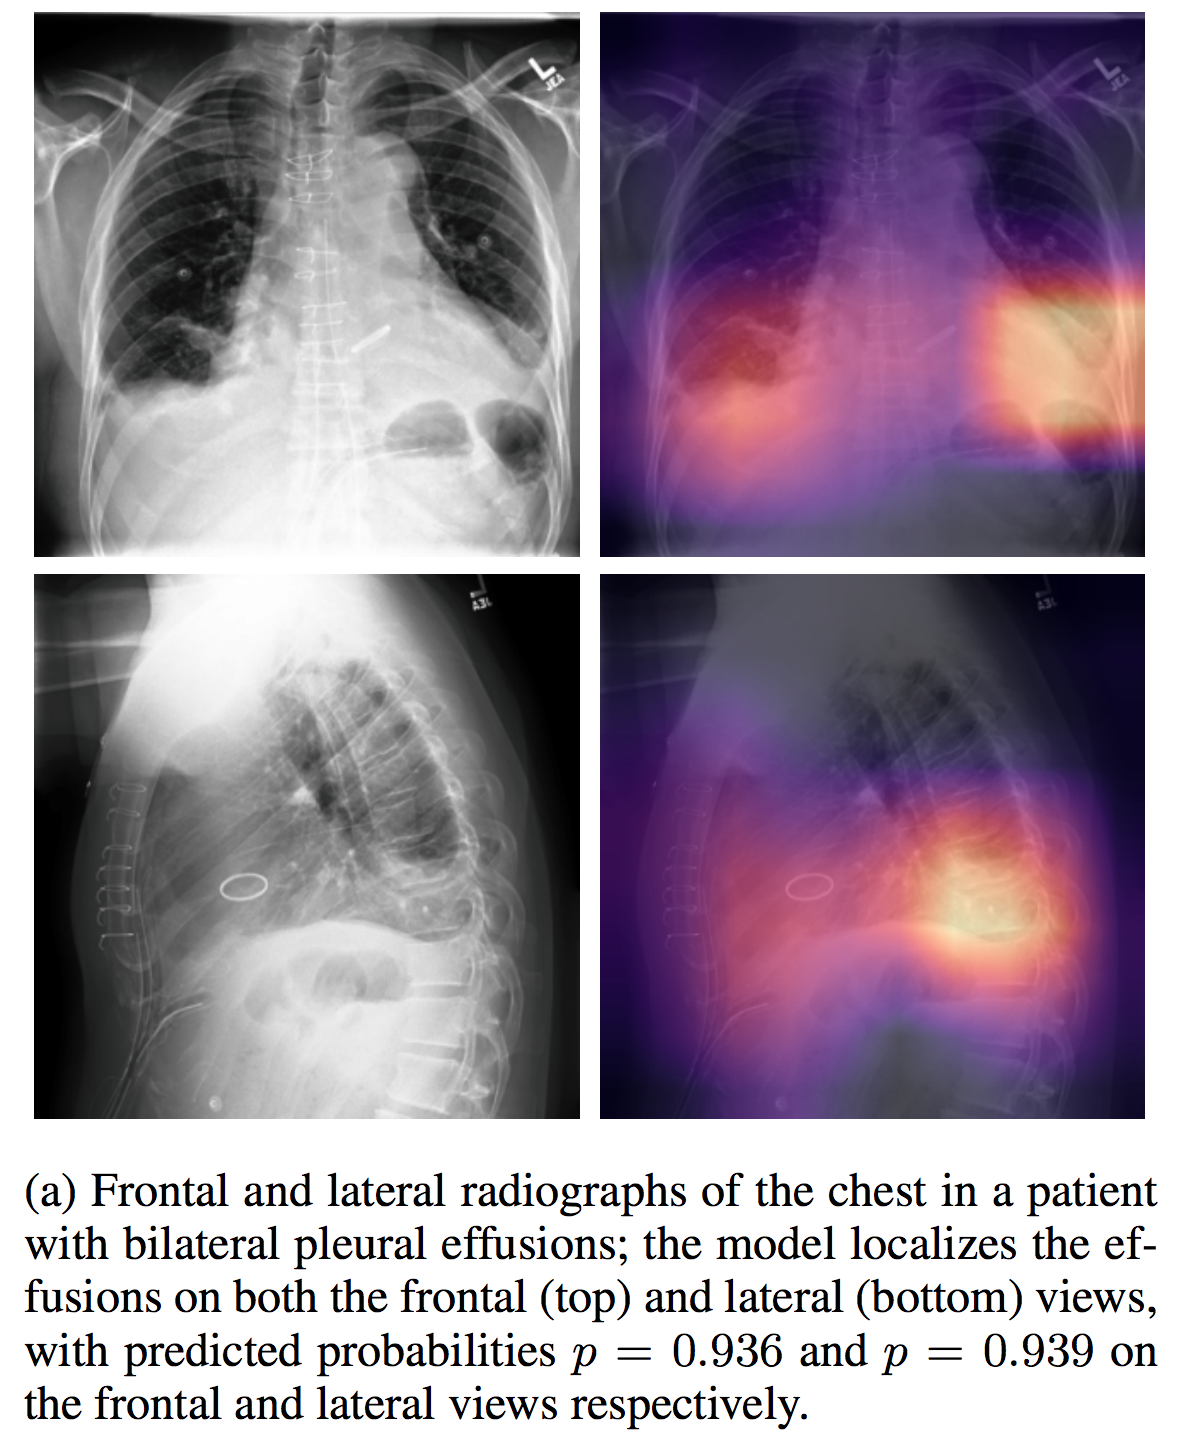

NIHChest Xray

| NIHChest Xray | 14种肺部疾病/部分病灶位置 | 分类/检测 | CXR | 112,120 | csv | png | CC0: Public Domain |

介绍论文: ChestX-ray8: Hospital-scale Chest X-ray Database and Benchmarks on Weakly-Supervised Classification and Localization of Common Thorax Diseases